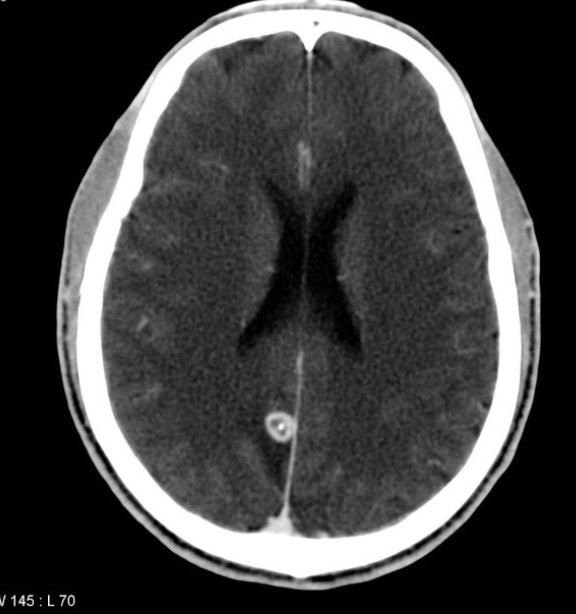

Seizures in a child returning from Mexico should prompt evaluation for this infection.

What is neurocysticercosis?

- Most common cause of acquired epilepsy in low-middle income countries (Latin America, sub-Saharan Africa, and parts of Asia most commonly)

- MRI/CT head: cyst with scolex (cyst with dot sign)

- Taenia solium exposure - can occur through contaminated food or water, or through autoinfection in tapeworm carriers.

- Multiple cysts common

- Treatment based on locations of the cysts - consult ID and neurosurg